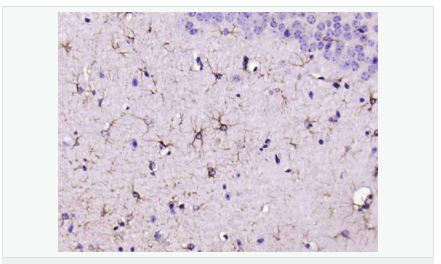

GFAP是一個56kDa的中間絲蛋白(intermediate filament,IF),在中樞神經(jīng)系統(tǒng)發(fā)育期是一個特異性的標志物,以區(qū)別星形細胞和其它膠質(zhì)細胞。GFAP表達在皮層和海馬,急、慢性皮質(zhì)酮治療時表達減少。

GFAP可以和人、大鼠、小鼠的GFAP反應(yīng),在正常和腫瘤性的星形膠質(zhì)細胞陽性表達,而神經(jīng)節(jié)細胞、神經(jīng)元、成纖維細胞、少突膠質(zhì)細胞和這些細胞來源的腫瘤細胞陰性表達,主要用于星形膠質(zhì)瘤等中樞神經(jīng)系統(tǒng)腫瘤的診斷和鑒別診斷,GFAP的缺乏可導(dǎo)致AD病。

image.png